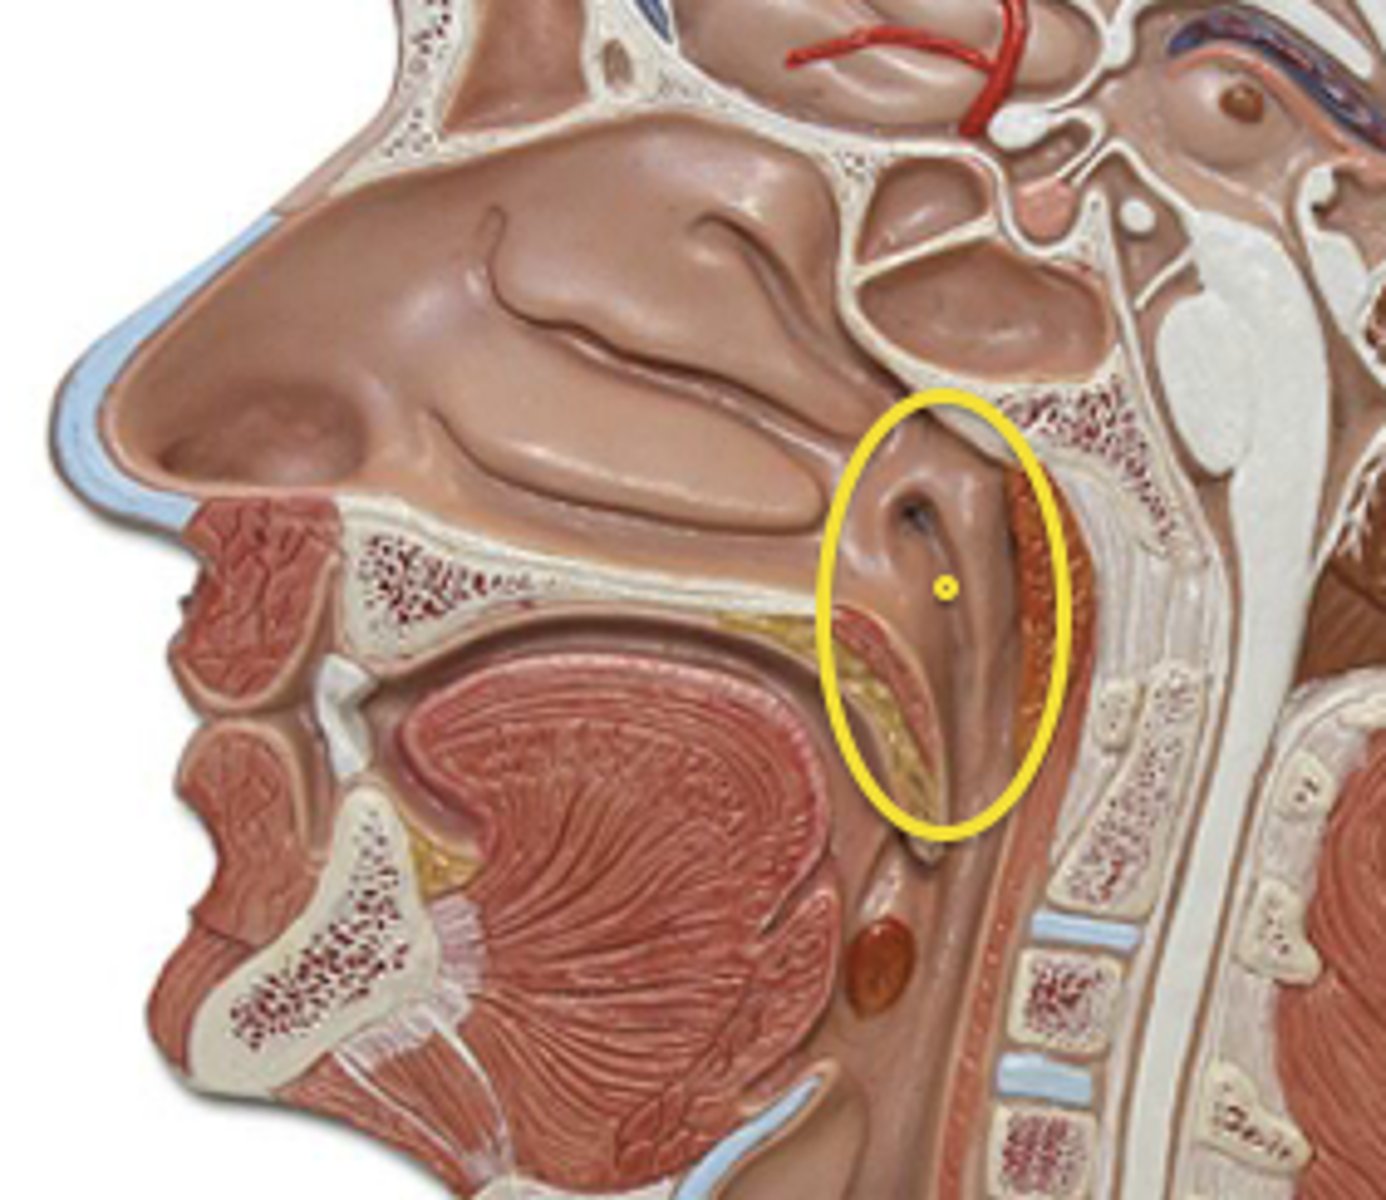

Pharynx

The membrane-lined cavity behind the nose and mouth, connecting them to the esophagus.

Nasopharynx

Region of the pharynx at the back of the nose and above the soft palate

Pharyngeal Orifice of Pharyngotympanic Tube

The base of the cartilaginous portion of the auditory tube

Oropharynx

Central portion of the pharynx between the roof of the mouth and the upper edge of the epiglottis

Laryngopharynx

Lower part of the pharynx, just below the oropharyngeal opening into the larynx and esophagus

Larynx

Voice box; passageway for air moving from pharynx to trachea; contains vocal cords

Epiglottis

A flap of cartilage at the root of the tongue, which is depressed during swallowing to cover the opening of the windpipe